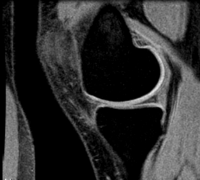

this is the fixed reference image. All images are aligned into this space lleft this is the moving image. The transform is calculated by matching this to the reference image LEGEND

lleft this indicates the moving image that determines the registration transform.

lleft T1 SPGR lleft T1 SPGR

0.9375 x 0.9375 x 1.2 mm

256 x 256 x 130

RAS

• Button green moving white.jpg moving: T1 SPGR , 0.9375 x 0.9375 x 1.2 mm voxel size, sagittal, RAS orientation.